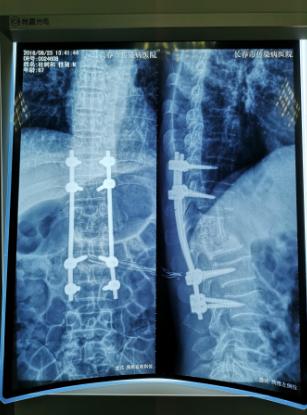

在长春市传染病医院骨科·普外科的走廊里,王大爷和老伴握着医生的手万分感激。光看他的脸色与精神,很难想象他曾经还是一位有下肢瘫痪的骨结核患者,结核杆菌在他的胸椎上肆虐大半年之久,侵蚀了多个椎体。但这一切已成为过去,在骨科·普外科全体医护人员的努力下,已经可以像正常人一样行走了。所幸的是,长春市传染病医院成功为其实施了脊柱畸形矫正、椎体结核侧前方减压灶清除椎间植骨术,为王大爷解除了疾痛,长春市传染病医院的手术是省内此类手术的领先水平。

经过检查,罗坚主任凭着丰富的临床经验初步认为王大爷患的是胸椎结核伴脊髓压迫症,那么是什么原因造成的?通过脊柱磁共振检查,罗主任发现王大爷患胸椎脊髓压迫的元凶正是“骨结核”。王大爷胸椎骨7-11节被结核杆菌严重侵蚀,在重体力活后,胸椎脊髓神经受到压迫,最终导致下肢瘫痪。同时患者双肺结核伴左上叶不张,左侧胸腔大量积液。如果等待双肺结核治愈,需时日很长,脊髓的受压如果不能及时解除,导致脊髓变性,那么瘫痪就难以恢复了,在积极治疗肺结核胸腔积液引流,罗坚主任为王大爷尽快安排实施手术。

手术过程中,病人腰大肌脓肿巨大,病椎破坏重游离死骨多,结核物质使脊髓严重受压,既要侧前方减压清除病灶,又要完成后凸畸形的矫正,再由于王大爷年龄较大、体质差,风险高,对技术与手术期管理都是很大的挑战。

罗坚、陈松峰和任重三位医师组成的团队实施手术。罗坚主任凭借其多年外科生涯中大量胸椎结核手术所积累的丰富经验,在脊柱侧前方减压,病灶清除、植骨和后凸畸形矫正胸膜外操作。手术按计划顺利完成,而辗转数家医院的“求医记”终于告一段落,在外等候的家人听到手术成功的消息后喜极而泣。